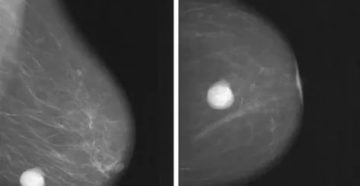

Киста молочных желез при климаксе Мастопатия – фиброзно-кистозное образование в молочной железе. Самый большой процент заболеваемости…